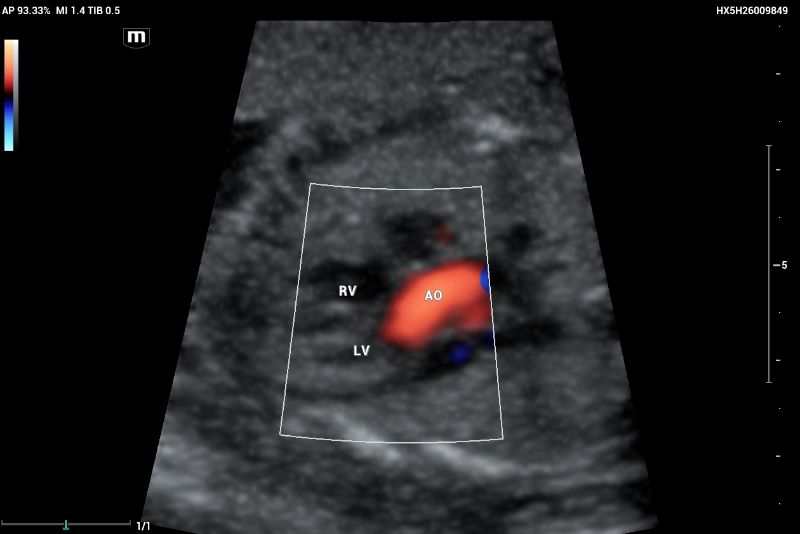

An example of normal echocardiography performed on Mindray Resona I9 system.  Artery–ventricle concordance showing the aortic outflow tract (AO) emerging of the left ventricle (LV)

Figure 5. An example of normal echocardiography performed on Mindray Resona I9 system. Artery–ventricle concordance showing the aortic outflow tract (AO) emerging of the left ventricle (LV)